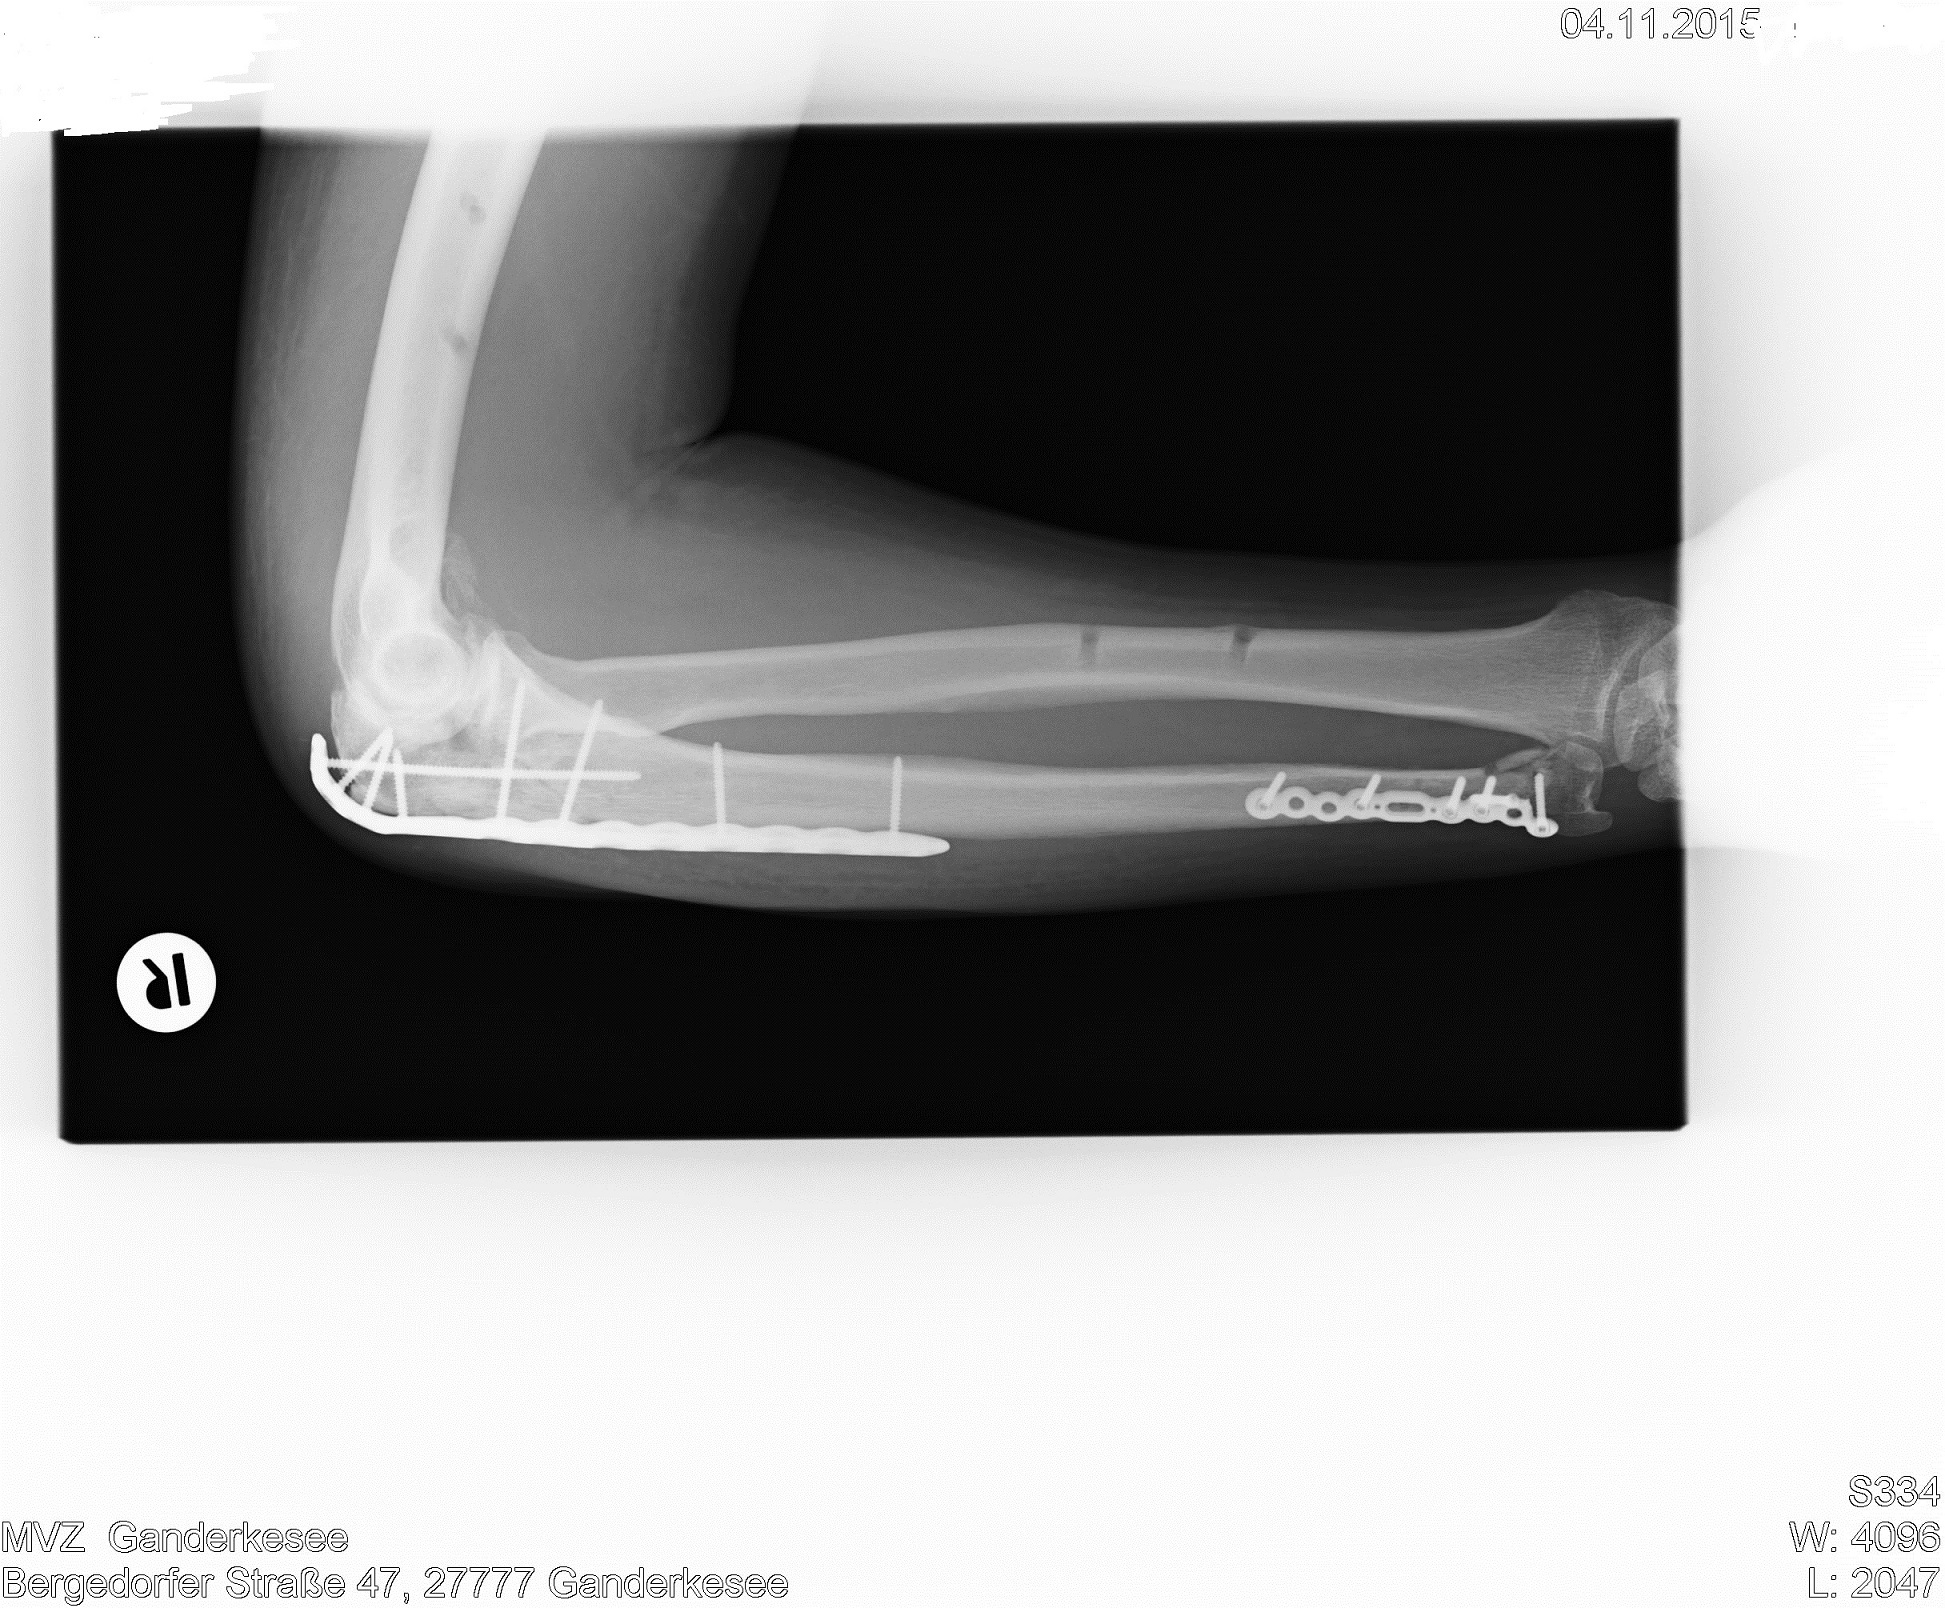

So sieht es im rechten Arm vom Meister aus 8O ----- sollte meinen Nickname ändern in "Don Blech" :rofl:

Na ja, ist wenigstens alles ganz gut zusammengewächst :D

Da wurde ja gut gepuzzelt! Hast n guten Schrauber gehabt. Weißt Du schon , wann das Blech raus kommt?

Ich hoffe es geht gut vorran. Die beiden Knicke in der Speiche wurden nicht begradigt und wachsen schief zusammen? Ich hoffe das wird gut. Physio ist auf jeden Fall das A und O dabei. Gute Besserung.